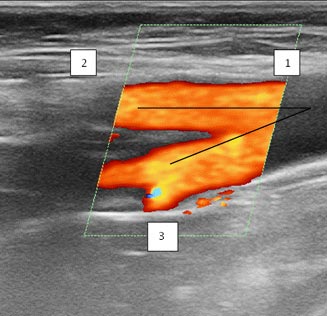

У пациентов группы А угол отхождения ГАБ составил 70–80°: у 13 (72,2%) пациентов он соответствовал 70°, у 3 (16,7%) пациентов — 75°, у 2 (11,1%) — 80°. RI составил 1,02±0,2 (р=0,009). К концу 1-го месяца значения RI достигли 1,24±0,1 и были достоверно выше, чем у пациентов группы В (р=0,000003) (рис. 3).

Рис. 3. Дуплексная сканограмма области бифуркации общей бедренной артерии у пациента из группы А через 1 мес: 1 — общая бедренная артерия; 2 — синтетический протез; 3 — глубокая артерия бедра (угол её отхождения 75°)